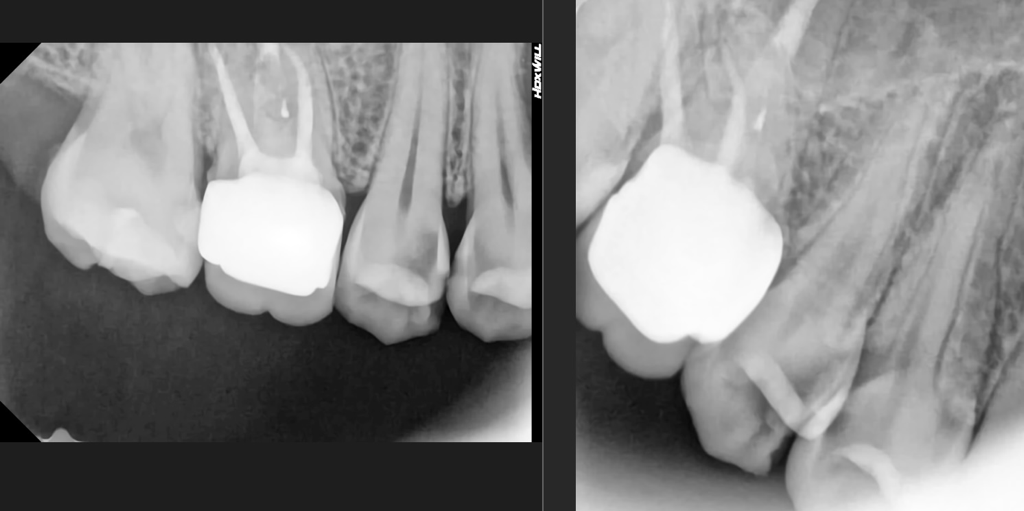

안녕하세요 평소 불편함이 있다고 생각을 못했는데 스케일링 받으러 갔다가 한 치아에 충치가 크다고 옆에 붙어있는 치아까지 두 치아 전부 인레이를 하던, 신경치료 후 크라운을 하자고 합니다. 외관상 제가 사진을 보니 한 치아는 충치가 심해서 구멍이 났어요. 근데 옆치아까지 신경치료 후 크라운을 하자고 하시고 제가 치과치료가 너무 무섭다고 하니 인레이로 최대한 해보자고 했습니다. 오늘 충치치료하고 인레이만 결제했는데 충치치료 끝물쯤 신경과 가까워서 아플 수 있다고 하셨고 실제로 아프고 시렸어요 마취를 했는데도. 제가 멀쩡한 치아도 마취하고 신경에 가깝게 치아를 깎으면 아플 수 있냐 하니 간호사 두 분이 대답이 다르고 의사분은 바빠보여 묻지를 못했어요. 일주일정도 시리고 불편하면 바로 크라운 하자고 하네요. 이 치아 둘 다 애초에 떼우는 걸로는 안됐던 치아였는지 궁금해서 질문드립니다. 검정 부분이면 썩은거라는데 비전문가인 저는 검정부분이 이빨 전체에 다 보여서 과잉진료인지 봐주세요..

• 2번 째 사진

• 사진으로만 봤을 경우에는 충치가 인접면에 매우 크게 있는 것으로 보입니다. 충치를 제거했을 때 신경이 노출이 된다면 신경 치료에 크라운 치료를 하는 것이 좋습니다. 인레이치료를 한다고 해도 범위가 넓기 때문에 보철물이 잘 탈락하거나 깨질 가능성이 높습니다. 자세한 확인을 위해서 치과에서 진료를 받아보는 것을 권해드립니다

엑스레이 상으로 보면 충치가 상당히 진행된 상태 같습니다. 저정도면 신경치료를 해야될 가능성이 높아 보이긴 합니다.

치아를 간단하게 치료하기에는 충치의 범위가 매우 큰 편이며 신경치료까지 하더라도 전혀 과잉이 아닙니다.

아래 그림에서 동그라미친 부분이 충치입니다. 충치가 신경(가운데 검은색 줄)과 근접해 있었기 때문에 충치 제거과정에서 신경이 간접노출 또는 완전노출되었다면 시리고 아팠을 수 있습니다. 이런 경우 신경치료는 불가피합니다. 다음 내원전까지 증상을 잘 살펴봐야 합니다.